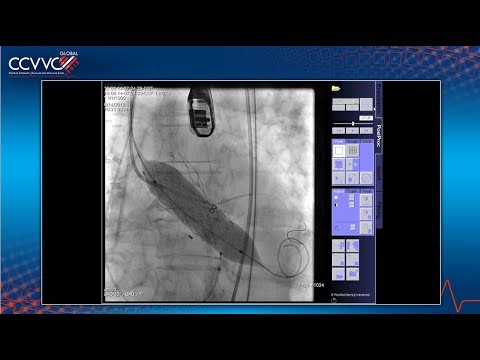

[AP VALVES & SH 2023] Live Case & Lecture 2: Complex TAVR

Transcatheter Valvular Techniques: Complex TAVR Case - Dr. Gian Paolo Ussia

[AP VALVES & SH 2019] Live Case & Lecture 1: TAVR #2